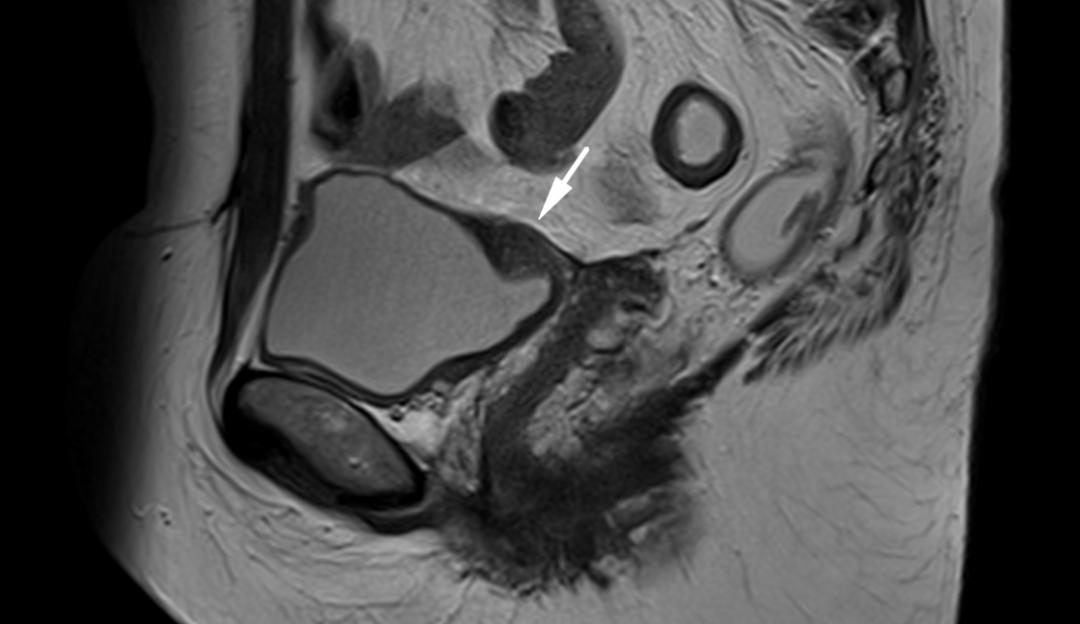

子宫内膜异位至左侧输尿管下段,T2WI 轴位和矢状位子宫颈左旁结节样低信号,边缘呈不规则星芒状,左侧输尿管扩张。

子宫内膜异位至直肠系膜,T2WI 轴位阴道左后方低信号结节,边缘星芒状,累及直肠系膜,但未累及直肠壁。